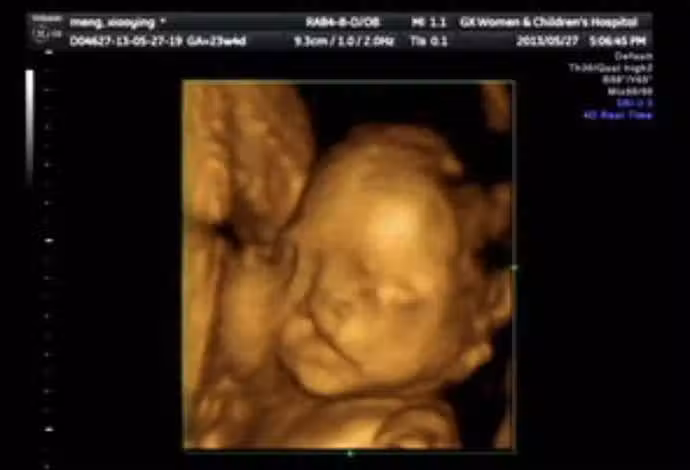

懷孕6個月!23歲孕媽照超音波「寶寶一直在笑」 醫生皺眉勸:「孩子不能留」...

突如其來的消息,讓年輕媽媽瞬間崩潰,不明白自己在孕期明明很注意了,為何還會有問題呢?後來經過詳細了解後,醫生終於找到了問題根本,原來女子在婚前的生活十分豐富,不但經常和朋友喝酒玩樂,甚至還菸不離手。雖然說婚後減少了許多夜生活,但是吸菸這麼多久,早就已經難戒掉了,「我在懷孕後也有繼續抽,身邊也有孕期抽菸的朋友,她們生下來的孩子都很健康」,所以她一直以為沒事,抱著僥倖的心態,結果竟然發生了不可挽回的憾事。